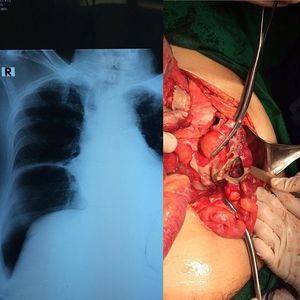

Colonic perforation, note the free air under the right hemidiaphragm